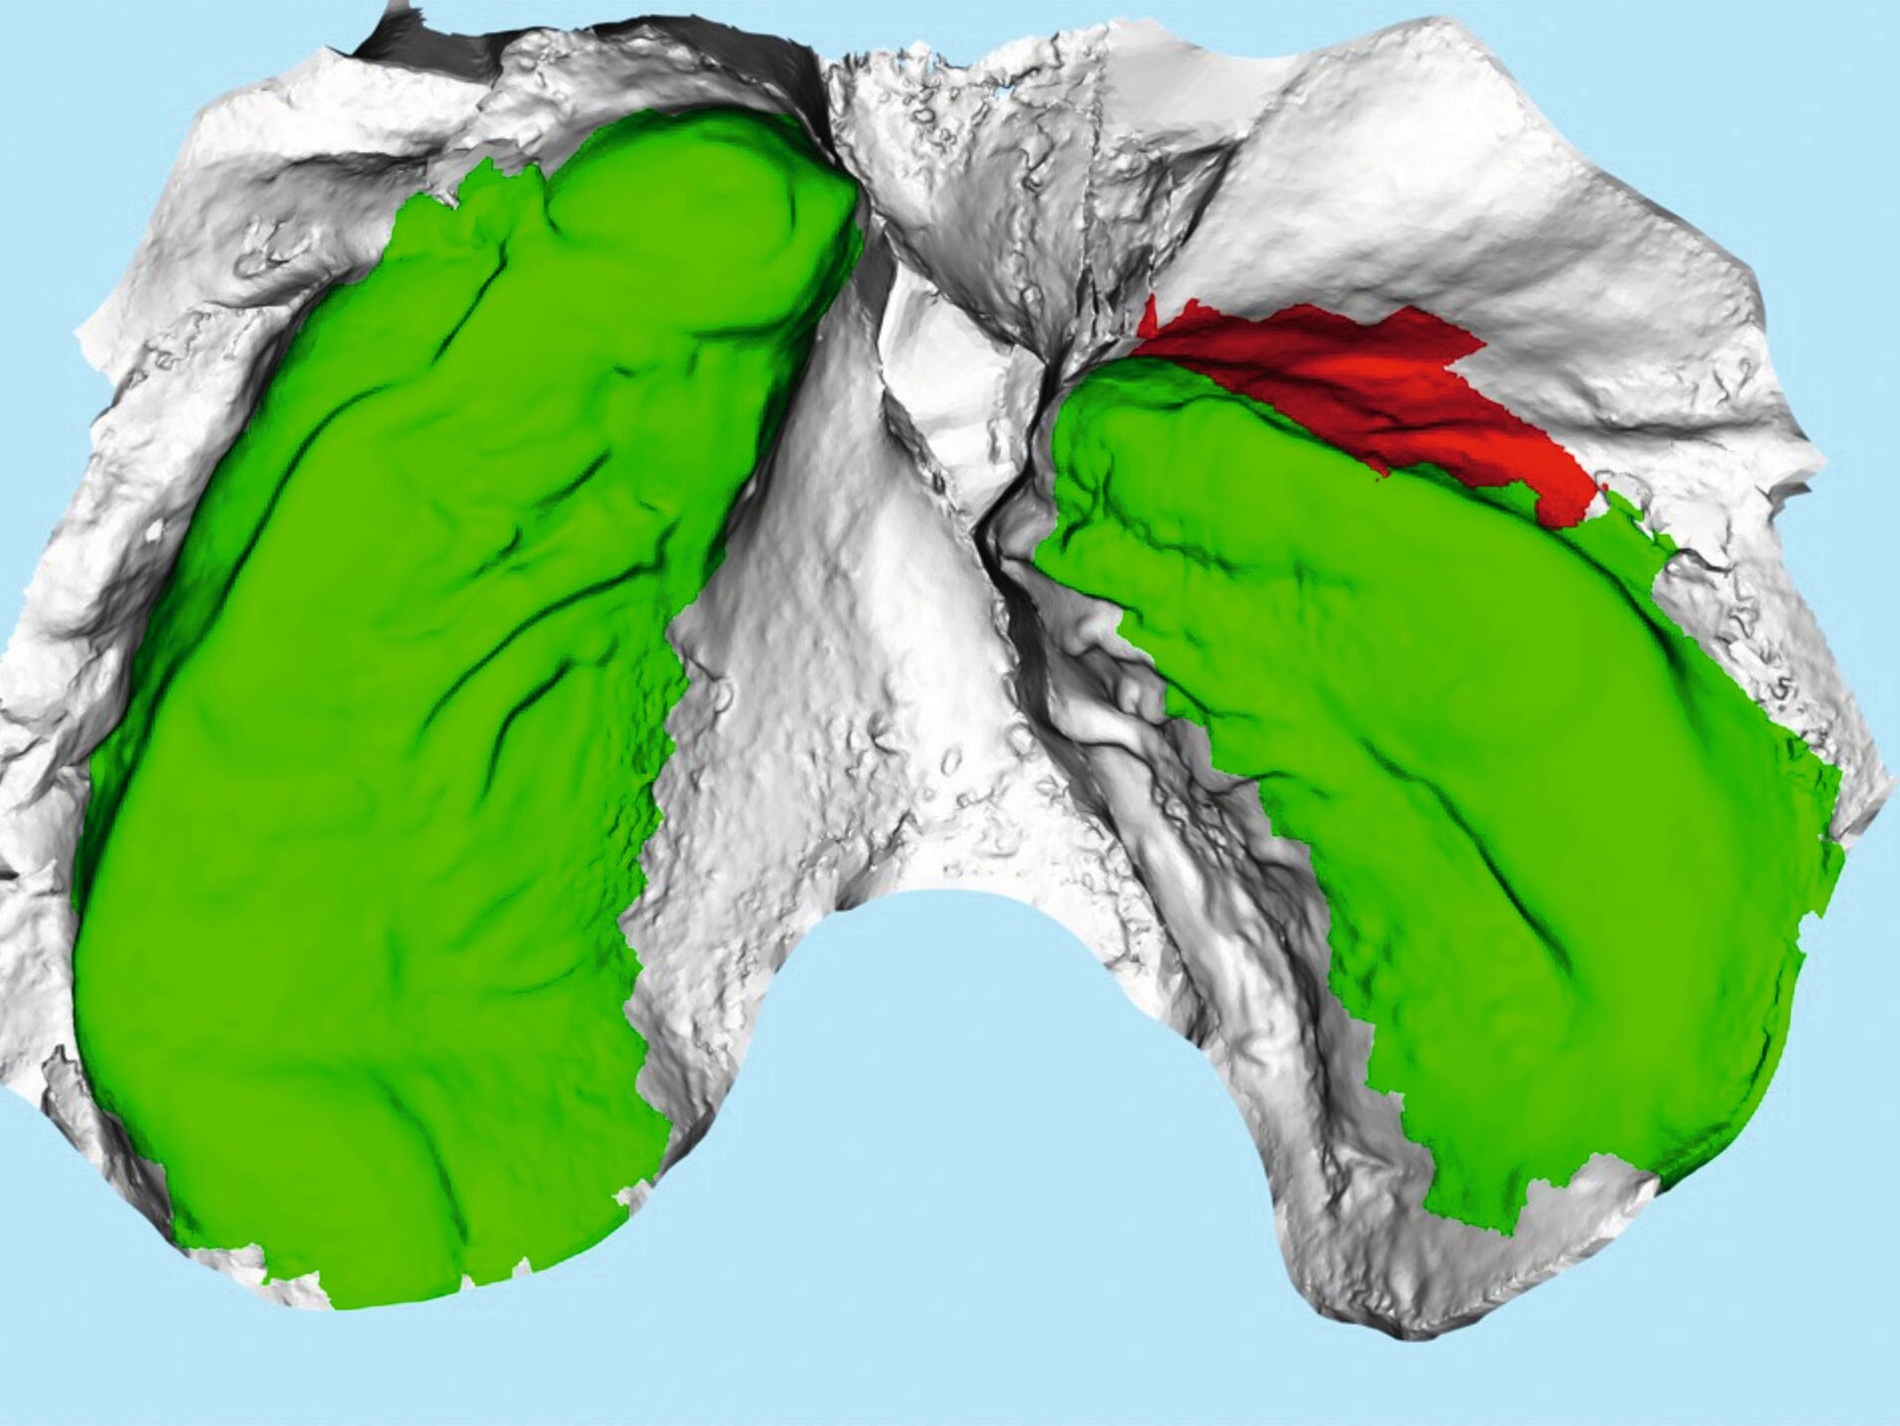

In Absprache mit dem/der zahnärztlich beziehungsweise chirurgisch tätigen Kollegen/in kann die Kieferorthopädie durch Umsetzung verschiedenster 3-D-gedruckter Elemente eine Hilfe in interdisziplinären Behandlungen bieten. Am Beispiel der Zahntransplantation ermöglicht der 3-D-Druck zuvor im DVT segmentierter Zähne eine passgenaue Vorbereitung des Transplantationsbettes (Abbildung 6a). 3-D-gedruckte Zähne können darüber hinaus als Lückenhalter während der kieferorthopädischen Behandlung dienen (Abbildung 6b), bevor eine definitive Versorgung durch den/die zahnärztliche/n Kollegen/in erfolgt.

Weitere Beispiele beinhalten hochkomplexe Behandlungsfälle multipler Zahnanlagen. Während die Extraktionsentscheidung und Absprache mit dem/der chirurgisch tätigen Kollegen/in allein auf Basis der Bildgebung oft limitiert ist, erleichtern 3-D-gedruckte Modelle des segmentierten DVTs sowohl die Entscheidung als auch die Absprache und ermöglichen darüber hinaus eine genauere Planung des chirurgischen Vorgehens (Abbildung 6c). Gleiches betrifft parodontalchirurgische Eingriffe, in denen sogenannte „Cutting guides“ eine zuvor digital geplante Gingivektomie ermöglichen (Abbildung 6d). Im Bereich der Freilegung verlagerter Zähne können Schablonen dem/die chirurgisch tätigen Kollegen/in sowohl die Freilegung des Zahnes (Abbildung 6e) als auch die Anbringung eines Attachments (Abbildung 6f) erleichtern und dabei die kieferorthopädisch gewünschte Attachmentposition passgenau übertragen.